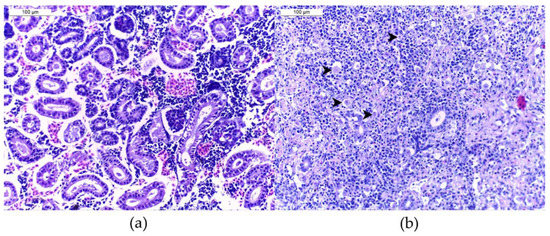

4.2. Histological Analysis